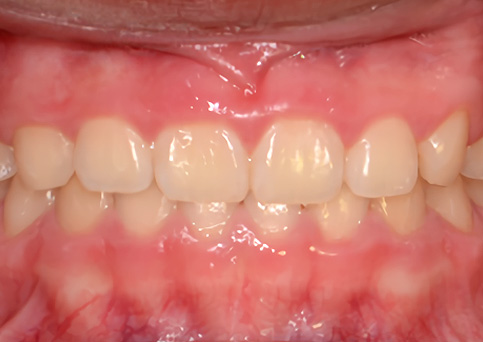

Anterior Cross bite

반대교합(주걱턱 예방)

주걱턱

주걱턱, 조기에 예방할 수 있습니다.

페이스마스크를 활용한 악정형 장치로 앞니 반대교합을 개선하고, 주걱턱을 미리 예방할 수 있습니다. 적절한 시기의 예방교정을 통해 자연스럽고 건강한 치열로 성장할 수 있도록 도와주었습니다.

• 주증상

전치부 반대교합

• 치료기간

약 6개월

• 부작용

치아표면의 탈회, 치은 부종, 치근흡수 등의 부작용이 있을 수 있습니다.